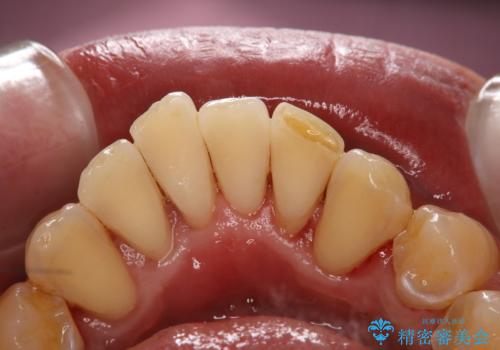

歯石除去で舌触りの変化

担当医 歯科衛生士